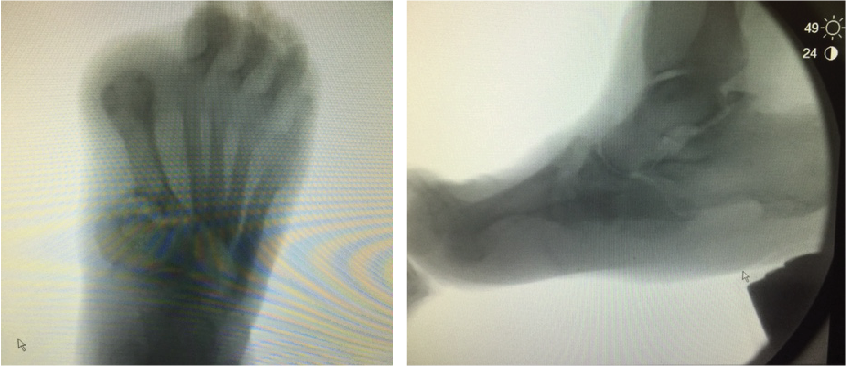

The most recognizable multiplanar deformity we have noted within this population is the pronated midtarsal joint. This is characterized by a loss of the medial longitudinal arch, abduction and possible supination of the forefoot. Bones of the lateral column are often superimposed with extrusion of the cuboid plantarly. Dislocation or fracture of the midfoot can occur at any of the midtarsal joints, producing a large bony mass medially. This deformity, although difficult to reduce, is often very amenable to a medial-based, truncated wedging.

The varus midtarsal joint deformity is a particularly unique presentation with its own challenges. On an AP radiograph, there may be near superimposition of the talus and calcaneus. The mechanism may include overpowering of the tibialis posterior tendon with lateral column defects in alignment of the cuboid and peroneal tendon dysfunction. There is simultaneous collapse of the medial column with an abnormal Meary’s angle as well. Treatment should include release of the tibialis posterior tendon and reestablishment of the Meary’s angle with medial beaming and joint preparation of all joint surfaces.

Placing beam screws with residual deformity can be challenging as the screw may not purchase healthy or substantial bone. For this reason, choosing the appropriate osteotomy is paramount. In instances of valgus collapse, physicians often utilize a medial-based wedge to correct the multiplanar deformity.

The ultimate goal of reconstruction is to create an osteotomy, which reestablishes an anatomic Meary’s angle on A/P and lateral views, and allows for the application of beam screws. We caution against the rote use of medial-based wedges. These wedges have limited indications and they may accentuate deformity in patients who have been selected inappropriately. Results from our institution indicate that medial-based wedges in patients with even small degrees of hindfoot varus produced significant accentuation of hindfoot varus.4 Forefoot to hindfoot position is critical when preparing for medial column fusion as any misalignment will make it difficult to enter the talus with your fixation.

In patients with obvious varus deformity, a lateral-based wedge or excision of the cuboid can reduce the deformity. In these cases, an element of stacking is often visible and surgeons must address it. In situations of a subtle hindfoot varus or valgus, utilize a translational osteotomy to realign the Meary’s angle and not accentuate the hindfoot position. We find that wedge osteotomy is insufficient and one can readily enhance it through the additional maneuver of cutting a through and through osteotomy, and rotating the forefoot on the hindfoot. Lateral fluoroscopy will show where to rotate as the “stacking” resolves. We have found that often patients who have had translational osteotomies benefit from repositioning of the subtalar joint.